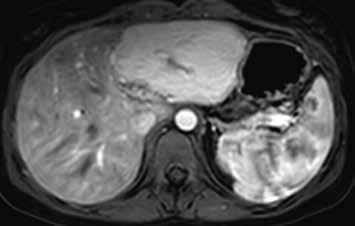

Již nativně jsou na T1-váženém obraze vidět vícečetná hyperintenzní ložiska (7). V arteriální fázi ložiska zůstávají hyperintenzní (8), v portovenózní fázi (9) a v hepatospecifické fázi (10) postupně splývají s okolním parenchymem.

Nativně je v jaterním parenchymu naznačeno několik minimálně hyperintenzních ložisek (13). Ložiska se zvýrazňují ve fázi arteriální (14) i portovenózní (15). V hepatospecifické fázi jsou nadále hyperintenzní (16).